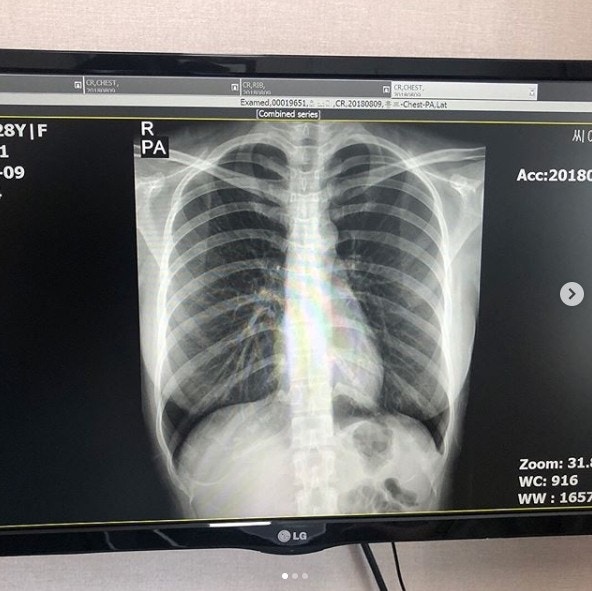

韓國人氣網紅 Choi Somi 外貌激似女星郭雪芙,因此有著「韓國郭雪芙」的封號,廣受臺灣粉絲喜愛,從不介意性感穿著的她,時常在網上分享自己的美照, 大方展露自己的傲人身曬,超惹火的上圍卻也為她招惹整形風波,面對網民質疑的聲音,去年,Choi Somi還因此在IG貼出胸部X光圖與醫師診斷書,證實自己的胸部是真的,大動作反擊也引發網友們對她的討論。

Choi Somi 胸部診斷書上寫著「沒有人工植入物」,也讓 Choi Somi 獲得清白,但當中還是有人抱持懷疑態度,認為診斷書可造假之疑慮。